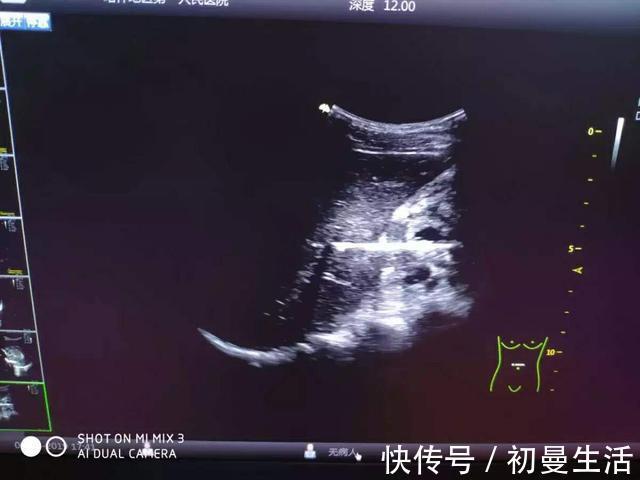

(超声显示条状强回声,穿透肠壁、刺入肝脏)根据在超声图像上显示的强回声,吴欢认为,很可能是金属、木头、塑料、橡胶等异物。最后,吴欢医生为小麦提做出了“腹部异物,异物穿透小肠壁刺入肝脏内”的诊断。拿到诊断结果的普外科医生,第一时间与小麦提积极、反复沟通。这时候小麦提才知道“纸包不住火”,终于向医生和父母坦白了。据小麦提说,今年5月,他看到电视里面有魔术表演,便心生好奇,想要学变魔术。为更加接近真实度,他找到了一根木棍,直直地将其吞进口腔。然而,体验感并不是很好,感觉到恶心的他立马将木棍拿出来,却发现木棍已少了一截。这个时候,小麦提慌了。与凭空“消失”的一截木棍相比,他更害怕被家人责骂。所以选择了保持沉默,直至出现腹痛发热的症状,也未说出“生病的真相”。如此反反复复,小麦提忍受了3个月的右侧腹痛发热。得知真相后,医生们经过多学科会诊,制订了诊疗方案,成功地在内镜下为小麦提取出了十二指肠降部的异物。没想到,让小麦提腹痛、发热的“元凶”,竟是一根近7厘米长的小木棍。